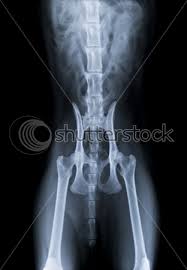

The pelvis's frame is made up of the bones of the pelvis, which connect the axial skeleton to the femurs, and therefore acts in weight bearing of the upper body. Male abdomen and pelvis ct scan form no 2: The cat has 230 bones, as opposed to 206 within the human body. Anatomy of the cat (pelvic limb) origin of sartorius. The purpose of this article is to review the three basic.

Study sets diagrams classes users. If you want to learn how to read ct scans of the abdomen and pelvis proficiently, this video is an excellent starting point. Ascending colon superior mesenteric vein superior mesenteric artery gonadal vessels linea semilunaris abdominal aorta linea alba inferior vena cava inferior mesenteric artery infe. Mri of the female pelvis: The slice thickness is 2.5 mm. ©ken l schreibman, phd/md 10/8/11 www.schreibman.info what to order when: The video covers the most clinic. Anatomy of the cat (pelvic limb) origin of sartorius.